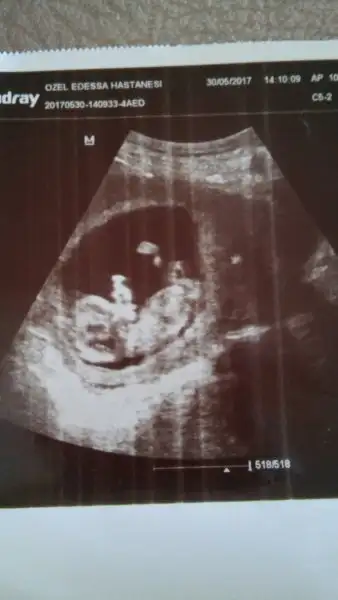

Kızlar bugün ikili tarama için gittim ense kalnlığı 0,178 çıktı burun kemiği oluşmış dedi ölçümlerin iyi olduğunu söyledi doktorum çok şükür inşallah tahlilde iyi çıkar. Cinsiyeti konusunda %60-80 civarı erkek dedi ama kesin konuşmadı yine de sizce nedir cinsiyeti bebeğimin??? baş kısmı sağda, ayak kısmı solda biraz tlefonda parlamış görüntüEki Görüntüle 2009584